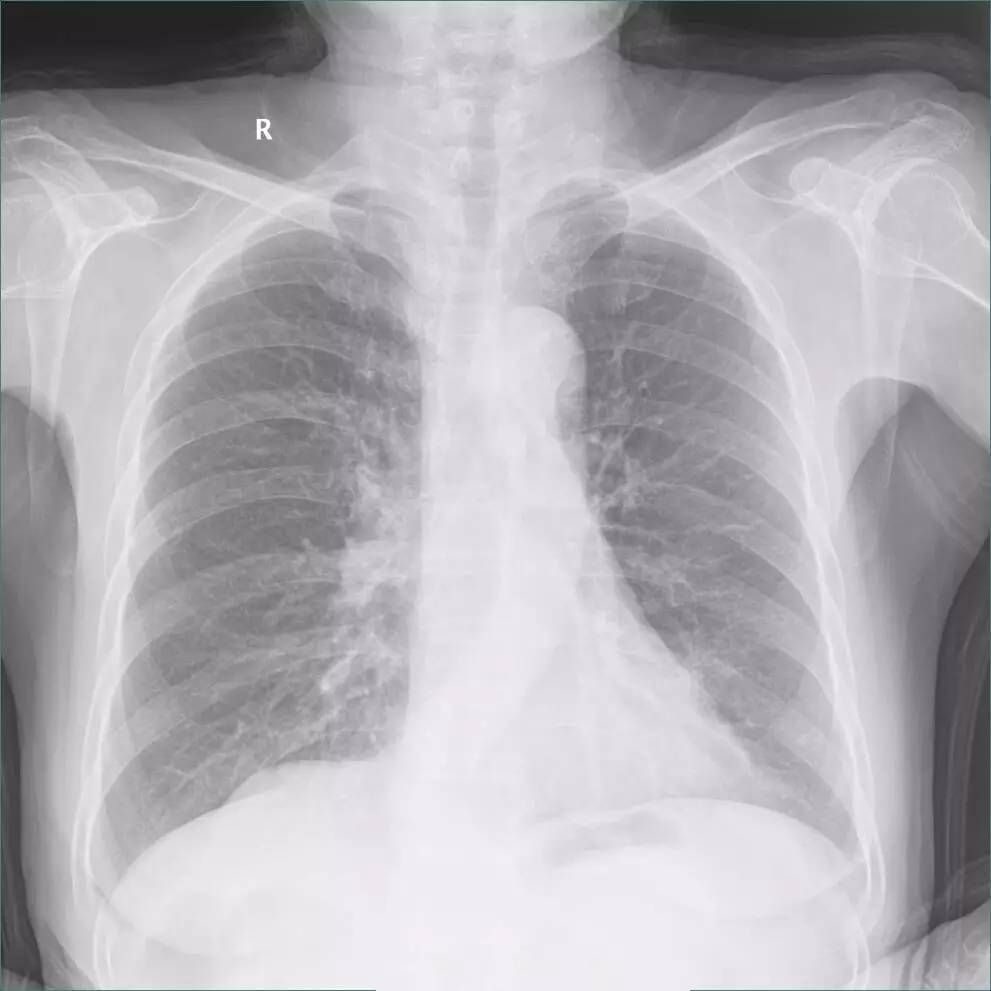

>>>>病例2:男,88y,右侧胸痛月余。

左下肺最有可能的诊断是?

A.包裹性积液

B.胸膜增厚

C.胸腔积液

D.心包脂肪垫